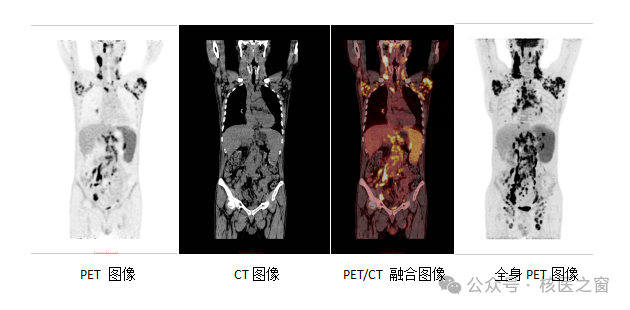

PET/CT是由PET和CT兩部分組成,因此檢查過程中的輻射也來自兩個方面:

1. PET的射線:來自體內(nèi)的放射性示蹤劑(主要來源)

PET部分的輻射主要來自注射進(jìn)身體的放射性示蹤劑。

示蹤劑進(jìn)入人體后,會在不同組織中分布和代謝,其釋放出的射線被PET探測器接收并成像。

臨床上最常用的示蹤劑是18F-FDG(氟代脫氧葡萄糖示蹤劑),用于反映組織的代謝活動。

2. CT的射線:來自低劑量的定位掃描

PET/CT中的CT部分主要用于提供準(zhǔn)確的解剖定位。

兩者圖像融合,有醫(yī)生對影像進(jìn)行分析,完成診斷